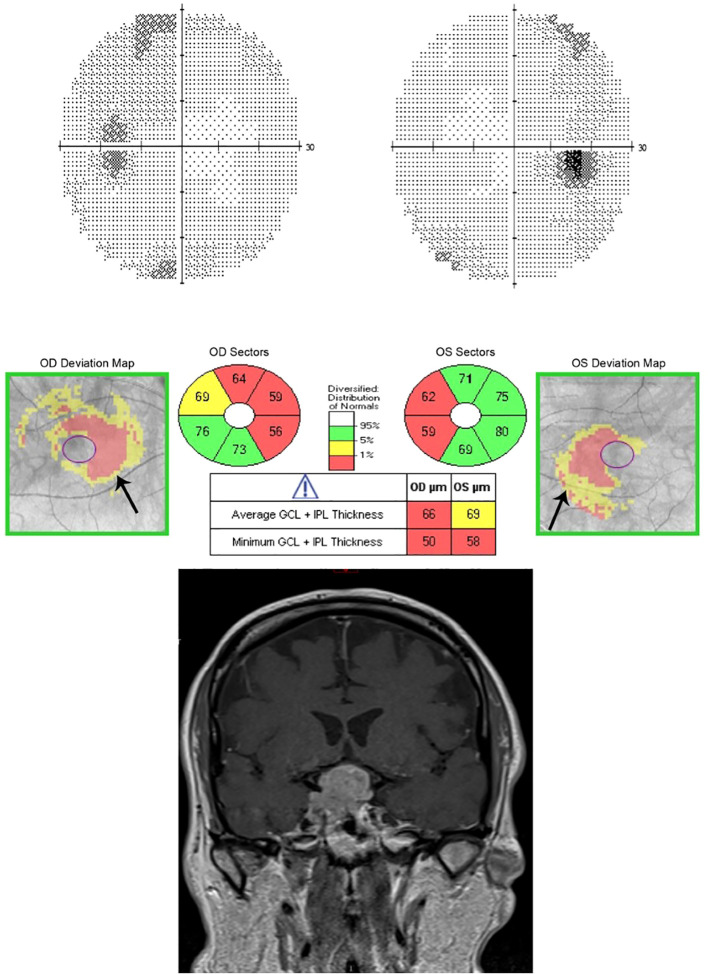

Sellar mases can cause a variety of neuro-ophthalmic manifestations, including compressive optic neuropathy, chiasmal syndrome, and ophthalmoplegia due to cranial nerve palsy. Diagnosis involves a thorough history, neuro-ophthalmic examination, and ancillary tests and investigations. Visual field testing is critical in diagnosing and localizing the lesion and determining the extent of visual field loss. Appropriate neuro-imaging is essential in characterizing and localizing the lesion. Neuro-ophthalmologic assessment include meticulous clinical examination and ancillary tests including,visual field testing, which is useful in localizing the lesion, and optical coherence tomography, which is helpful in assessing the degree of axonal and neuronal loss and predicting the visual outcome. Treatment requires a multidisciplinary approach by different specialties, including radiologists, neuro-ophthalmologists, and neurosurgeons. The two primary treatment modalities for these tumors are surgery and radiation therapy. We review the main types of sellar lesions, their neuro-ophthalmologic evaluation, and treatment options.